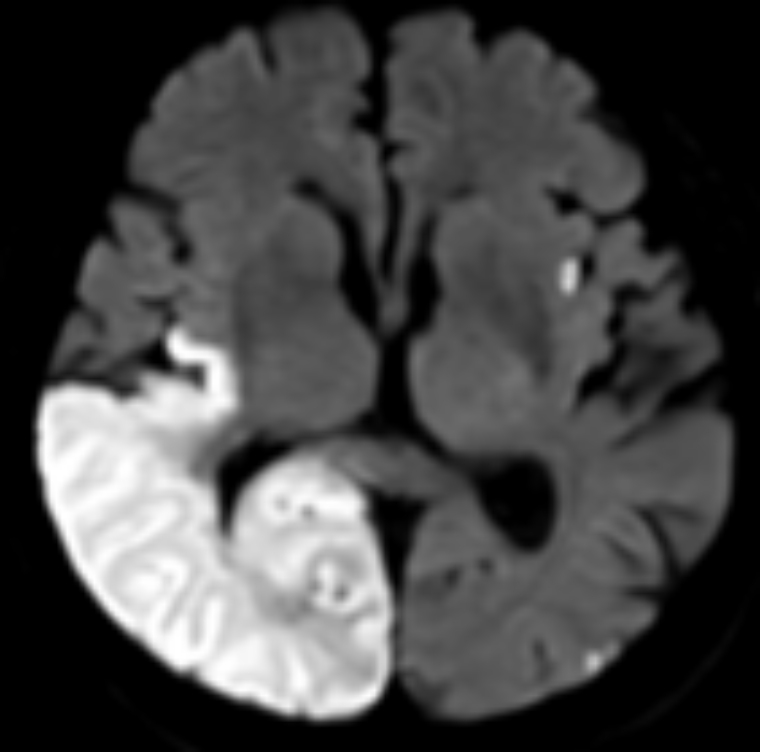

Il s’agit d’une étude observationnelle prospective. Son objectif principal est de décrire la prise en charge de tous les patients victimes d’un évènement neurovasculaire (AVC ischémique ou hémorragique et AIT) adressés à une structure d’urgence. L’étude réalisée 2 fois par an, est à l’échelle de la région sur une durée de 15 jours.

• Types d’imagerie (TDM, IRM, …)

• Thérapeutiques entreprises (thrombolyse, thrombectomie, …)